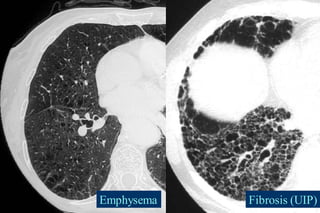

Emphysema Fibrosis (UIP)

Fibrosis and Emphysema

Emphysema

Emphysema typically presents as

areas of low attenuation without

visible walls as a result of

parenchymal destruction.